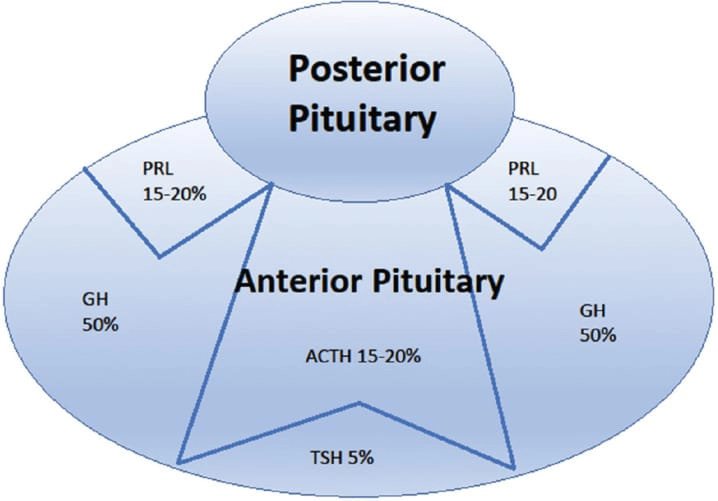

পিটুইটারি গ্রন্থি দু’টি প্রধান ভাগে বিভক্ত: অ্যান্টেরিয়র (সামনের) ও পোস্টেরিয়র (পিছনের) লোব। মানুষের ক্ষেত্রে ইন্টারমিডিয়েট লোব থাকলেও তা স্বতন্ত্র অংশ হিসেবে গঠিত নয়। অ্যান্টেরিয়র লোব অপেক্ষাকৃত বড় এবং পুরো গ্রন্থির প্রায় ৮০% ওজন ধারণ করে।

* পিটুইটারি গ্রন্থি যে গুরুত্বপূর্ণ হরমোনগুলি নিঃসরণ করে তার মধ্যে রয়েছে:

1. গ্রোথ হরমোন (Growth Hormone - GH)

2. থাইরয়েড স্টিমুলেটিং হরমোন (TSH)

3. প্রোল্যাকটিন, ইত্যাদি।